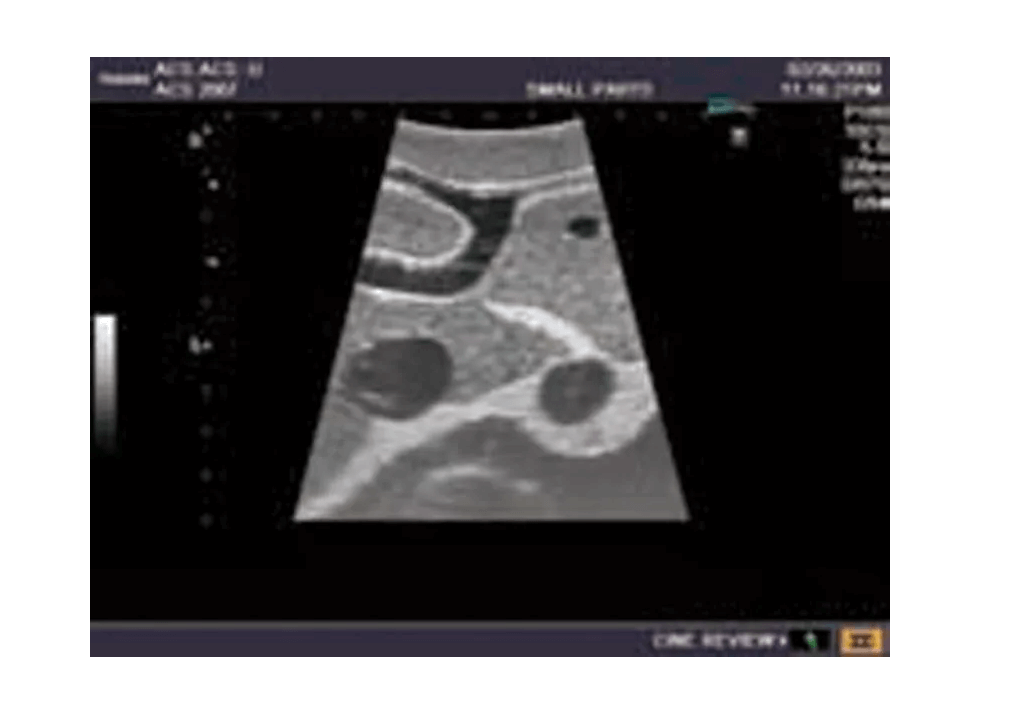

Das Ultraschall-Modell für Sonografie ist speziell für die Ausbildung von Anfängern und die Demonstration durch Fachleute konzipiert. Es bietet eine detaillierte und realistische Darstellung der Anatomie des Abdomens, einschließlich der Leber, Gallenwege, des Pankreas und der Nieren. Das Modell erfüllt die höchsten Anforderungen an eine exzellente Ausbildung und ermöglicht die Durchführung von offenen intraoperativen Sonografien sowie laparoskopischen Untersuchungen, um etwaige Läsionen und Steinbildungen zu prüfen. Es umfasst eine Vielzahl von Läsionen wie Gallensteine, Zysten und Tumore, die in den verschiedenen Organen simuliert sind, um realistische Übungsmöglichkeiten zu bieten.

Simulierte Läsionen (solide Tumore, Zysten, Gallensteine) in wichtigen Organen für praxisnahe Ausbildung

Integrierte Simulation von organischen Läsionen und Tumoren, die in die Organe eindringen, für die Übung und Diagnostik

Die Simulation von pathologischen Befunden wie Tumoren, Zysten und Steinbildungen ermöglicht eine umfassende Vorbereitung auf die Ultraschalldiagnostik